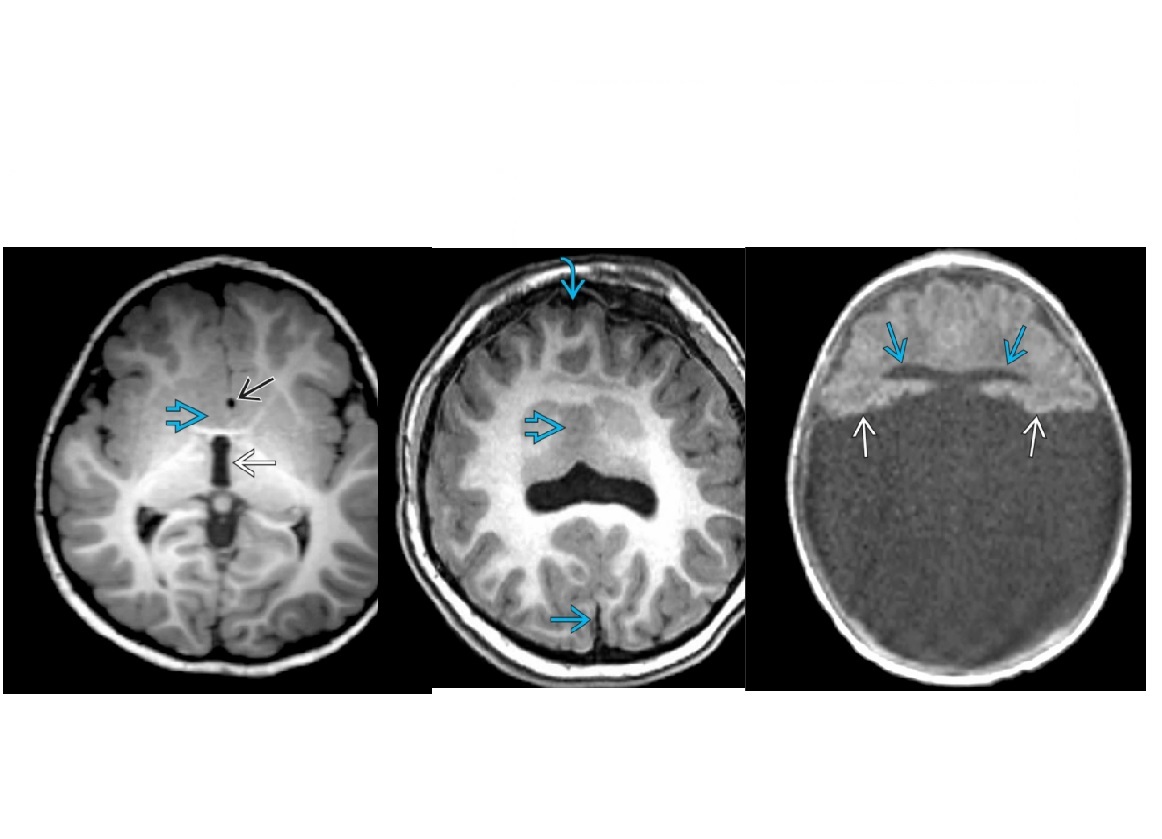

Q

Monoventricle, thalami and basal ganglia are fused?

A

Alobar Holoprosencephaly

Addition: Most severe form.

**No falx or corpus callosum

Complete absence of cleavage with “pancake” of anterior cerebral tissue, crescent-shaped anterior monoventricle communicating with large dorsal cyst,** fused thalami**

How well did you know this?

5

Absent septum pellucidum ?

Lobar Holoprosencephaly

Mildest from of holoprosencephaly

Cleavage is apparently back to front (opposite the corpus callosum ) so posterior fossa is normal in mildest form

Interhemispheric fissure & falx are mostly formed with partial nonseparation of frontal lobes